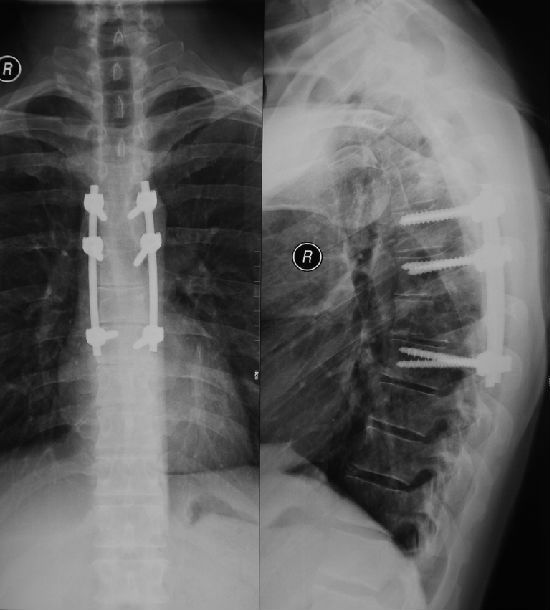

术后x线片示胸椎6,7椎间隙后部相邻终板和椎体切除术后矢状位ct示胸6

图片尺寸550x610